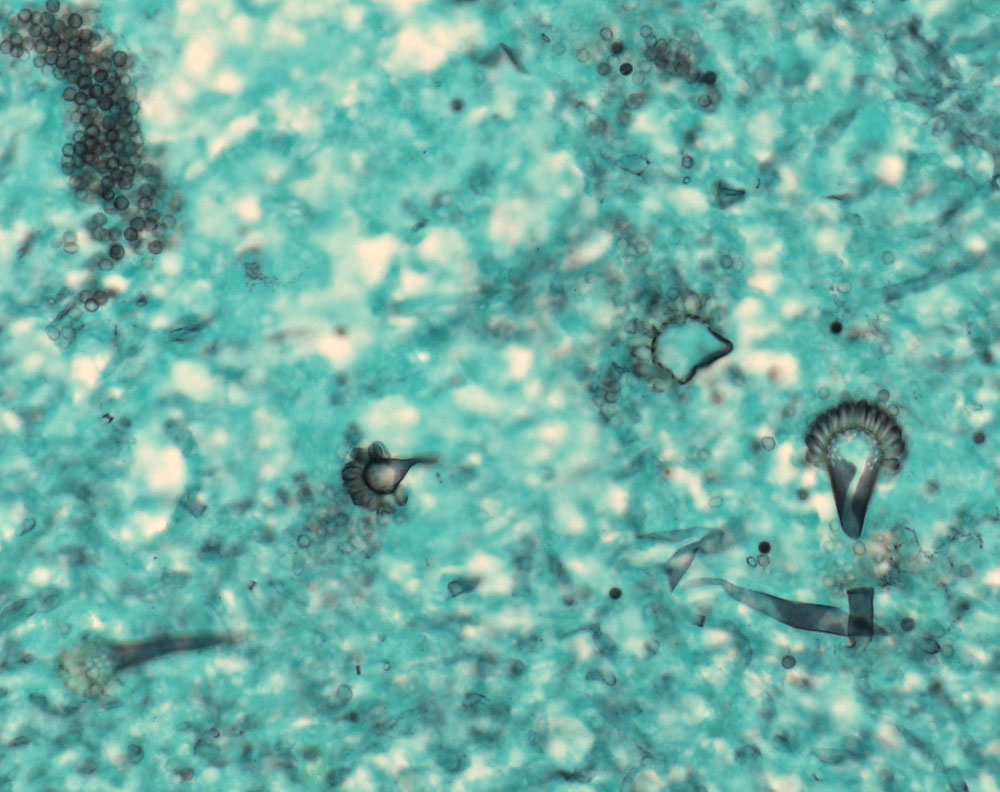

Fungale Sinusitis mit Pilzball (Aspergillom)

Ausschnitt aus dem Pilzball mit mehreren Fruchtköpfen (Conidiophoren) und aufgequollenen Aspergillushyphen.

Chronische Sinusitis maxillaris und ethmoidalis rechts (Aspergillus). Detritus und Nasennebenhöhlenschleimhaut.

Aspergillen gehören in die Gruppe der Schimmelpilze und wachsen ubiquitär auf organischen Stoffen. Der Erreger ist charakterisiert durch echte septierte Hyphen von 3 bis 6 Mikrometer Durchmesser. Die Hyphen verzweigen sich in einem Winkel von 45 Grad. Fruchtköpfe (Conidiophoren) sind selten nachweisbar. Aspergillusinfekte manifestieren sich je nach Resistenzlage in folgenden Formen der fungalen Rhinosinusitis: